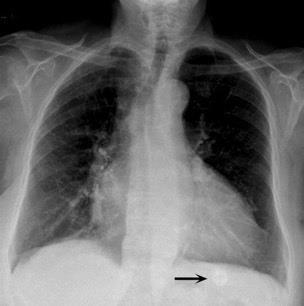

Nódulo en língula.

Cirugía de Ca .de mama hace 23 añosedema de brazo y ganglio en axila. ¡Metástasis!.

Ecanow JS et l. Axillary Staging of Breast Cancer: What the Radiologist Should Know. Radiographics 2013